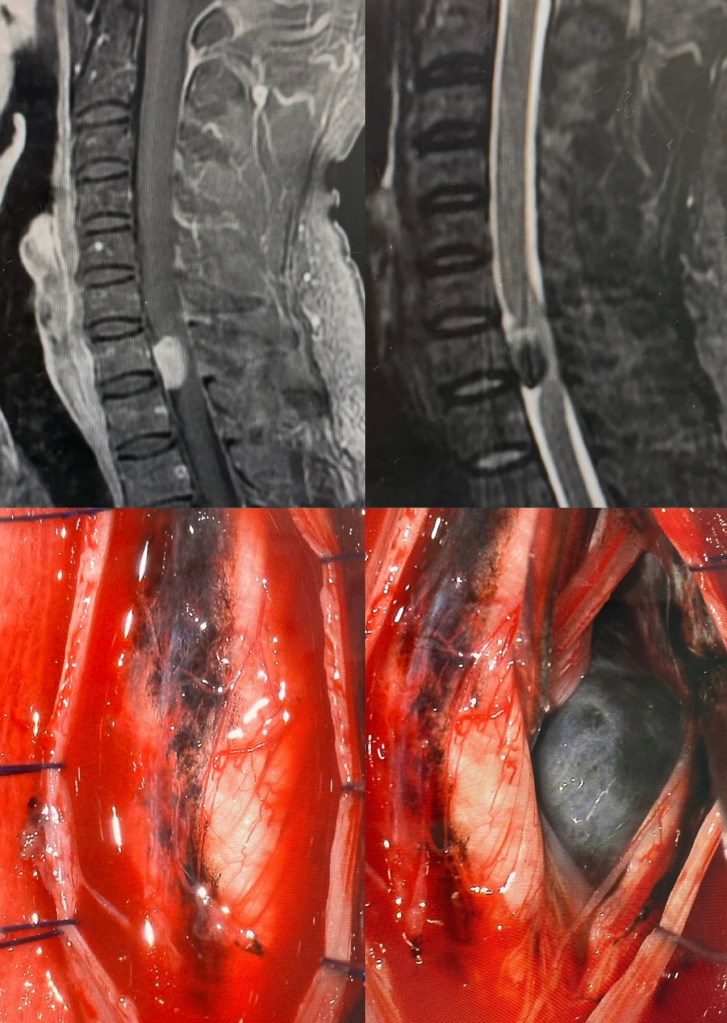

GALERIA De cirurgias

Abaixo você pode conferir imagens de algumas cirurgias já realizadas por Dr. Marcelo Camargos. Caso tenha alguma dúvida ou interesse, não deixe de fazer contato para maiores esclarecimentos!